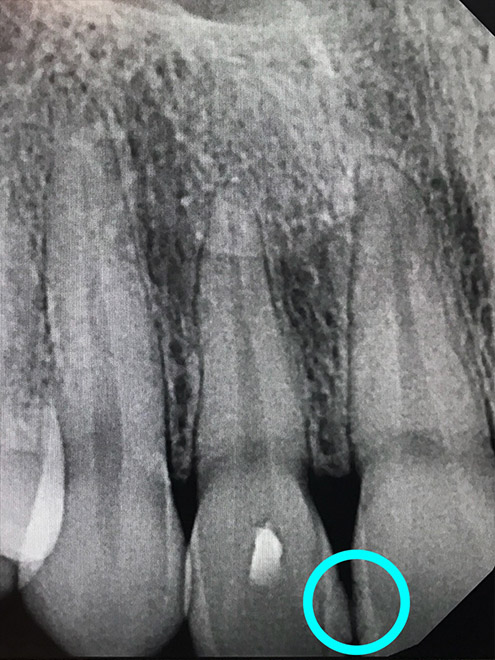

Bone healing with ozone treatment and SRP

Reverse Gum Disease: Bone Healing